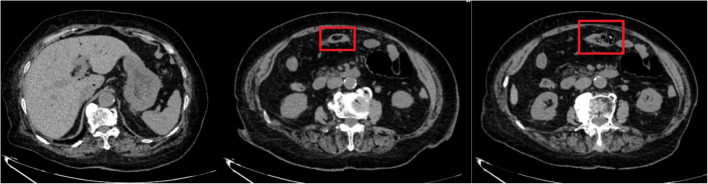

Case presentation: We present a clinically instructive case of a nonagenarian female initially diagnosed with colonic pneumatosis through imaging studies. Subsequent diagnostic reevaluation revealed progressive colonic necrosis requiring emergent surgical intervention. The patient underwent successful segmental colectomy with colostomy, achieving full recovery and discharge within 14 postoperative days.

Conclusion: This case highlights three critical aspects in managing geriatric patients with acute abdominal emergencies: The inherent diagnostic limitations posed by atypical presentations in elderly populations, including unreliable history-taking and attenuated physical signs; The insufficient sensitivity of conventional laboratory markers (leukocytosis, NEUT%, PCT, lactate elevation) for detecting intestinal ischemia; The pivotal role of contrast-enhanced computed tomography (CT) in surgical decision-making, particularly the prognostic significance of non-enhancing bowel wall dilatation as a radiographic hallmark of transmural necrosis. Early surgical consultation and protocolized CT interpretation are paramount for optimizing outcomes in this high-risk patient cohort.